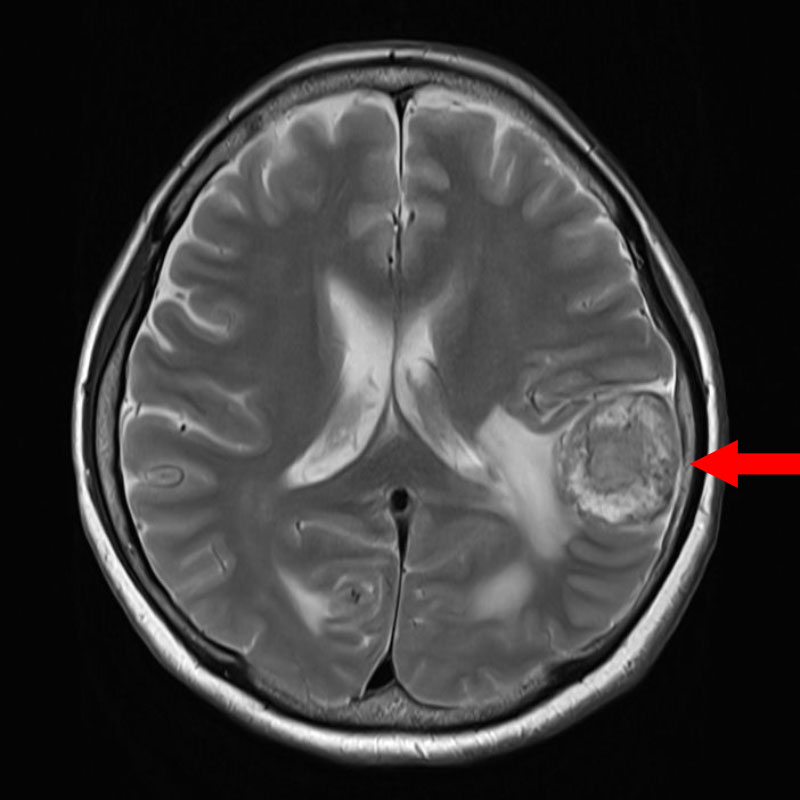

706

'25年12月

80代

右頭頂葉腫瘍

頭蓋内腫瘍摘出術